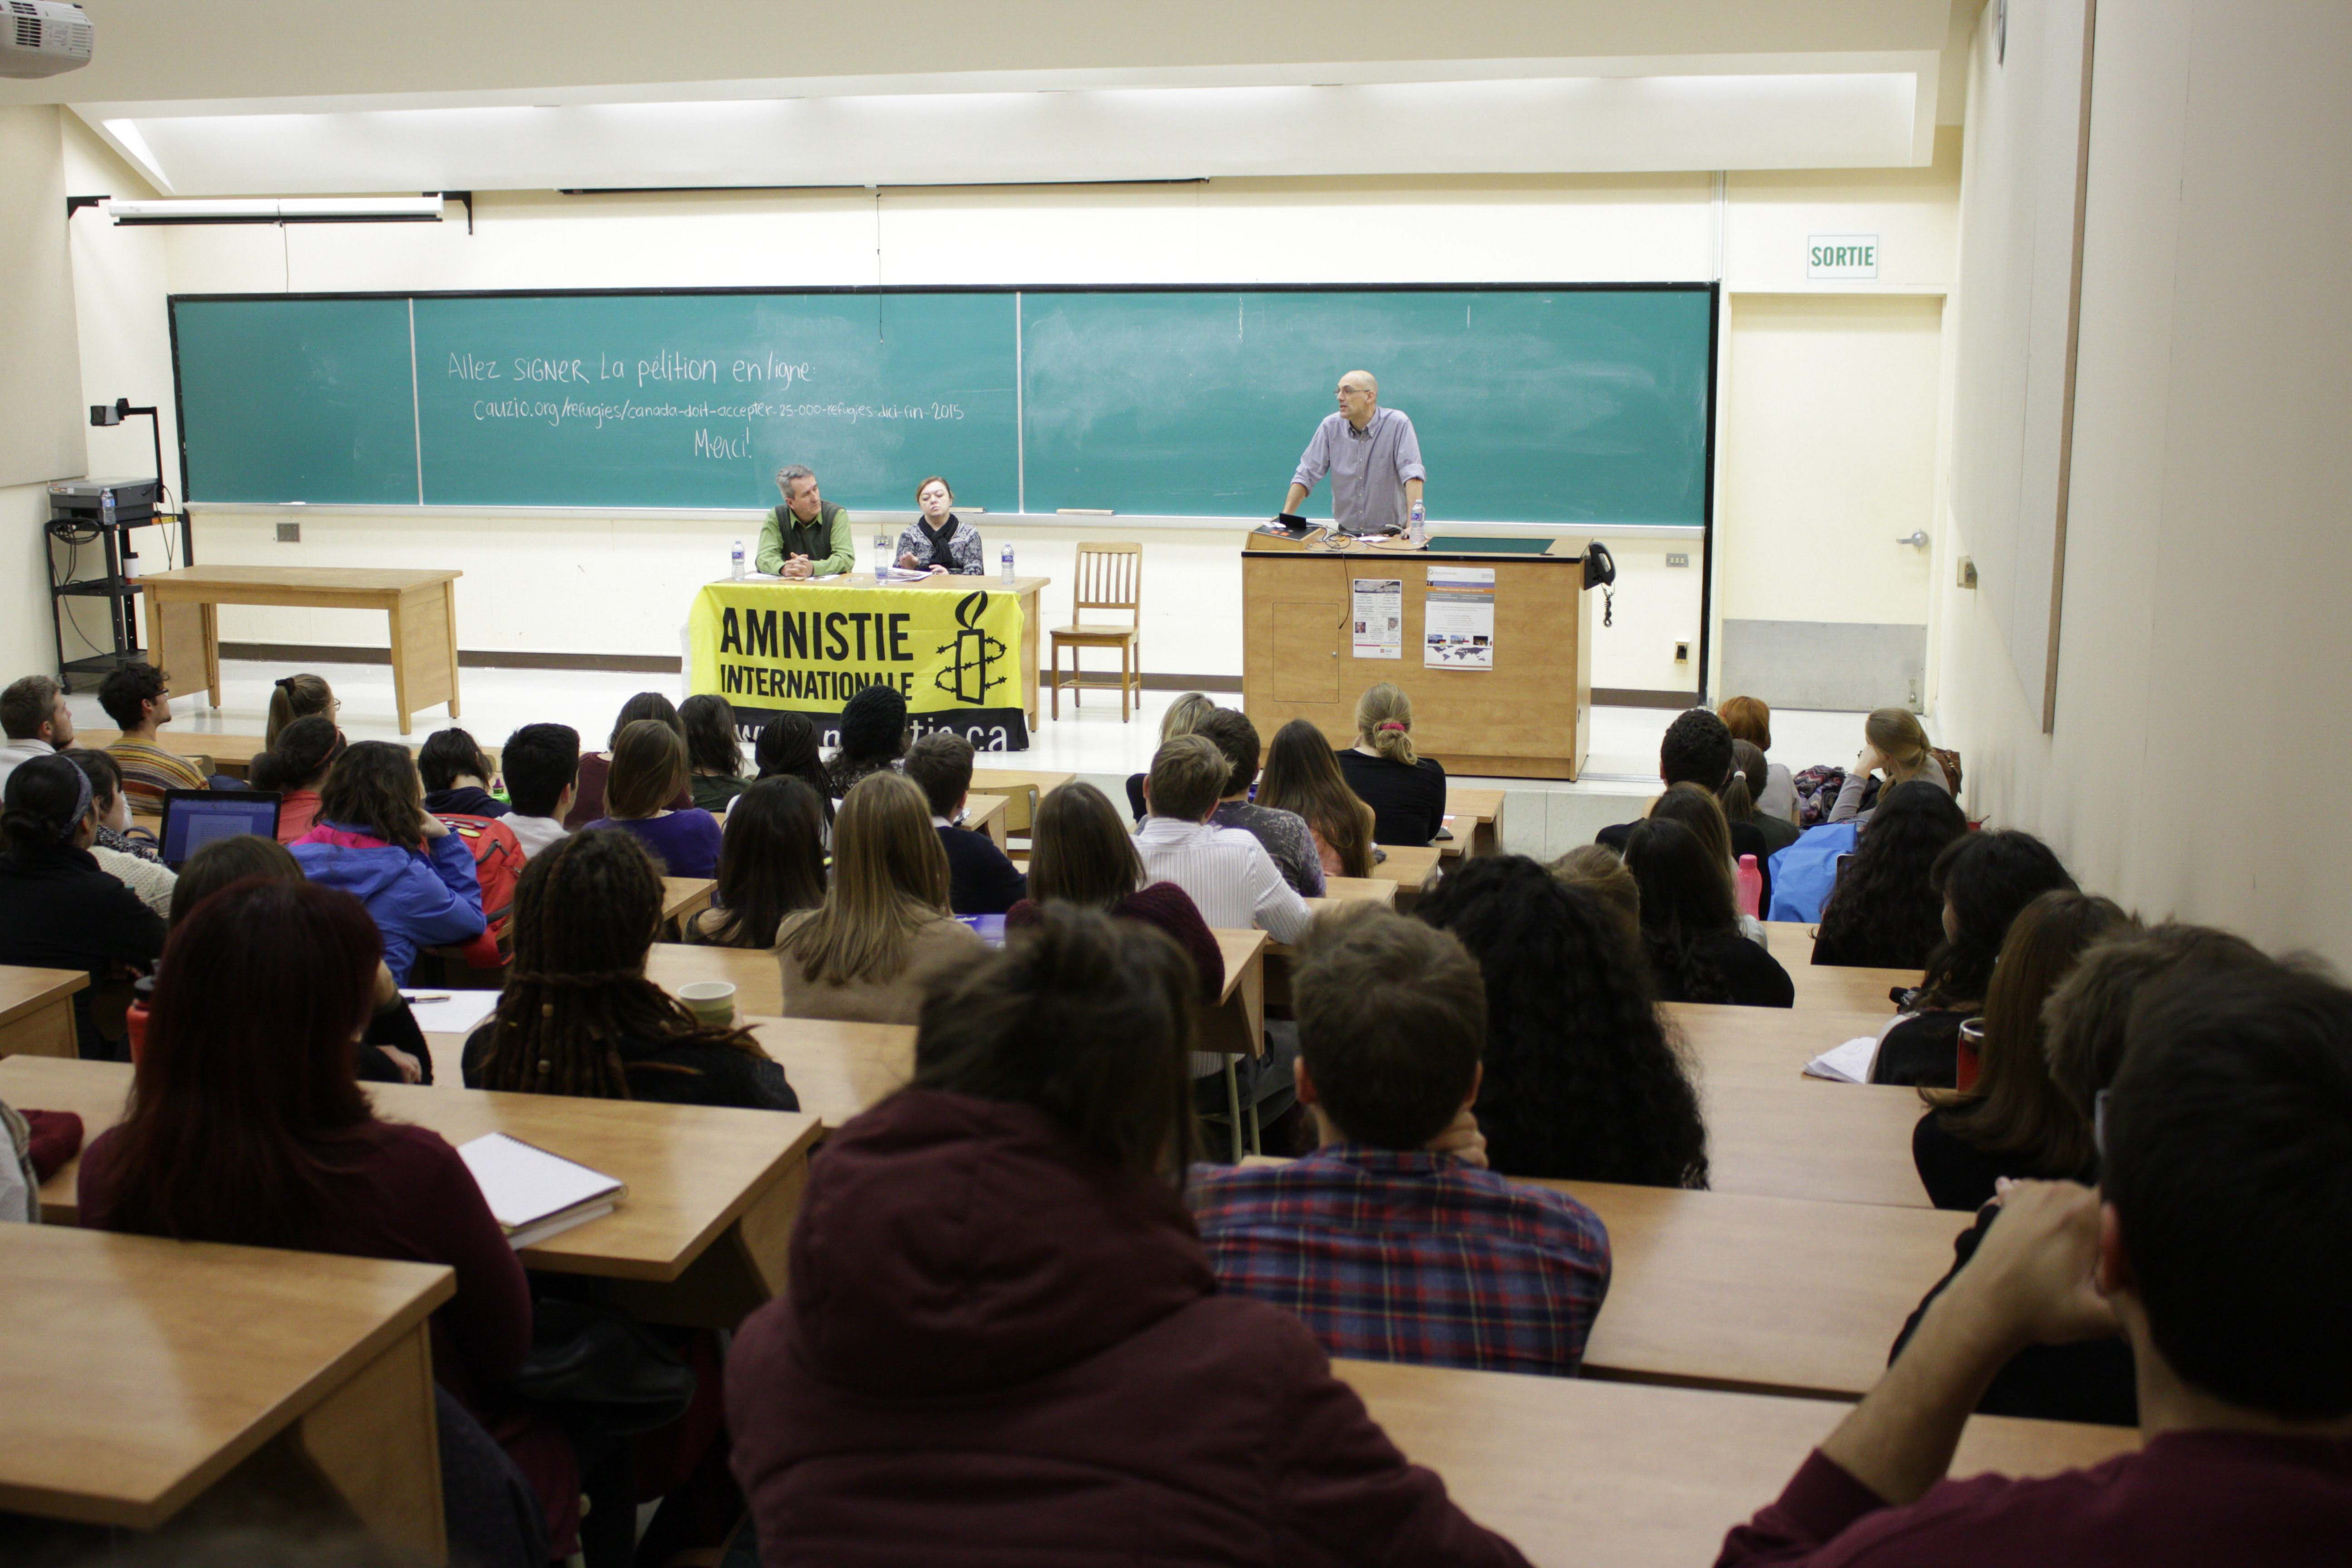

Considérations éthiques au pays des études cliniques

Sous promesse d’obtenir de généreuses compensations monétaires, de nombreux étudiants se portent volontaires pour participer à des études cliniques menées pour le compte de compagnies pharmaceutiques. Une pratique tout à fait légale qui, bien que nécessaire à l’élaboration de nouveaux...